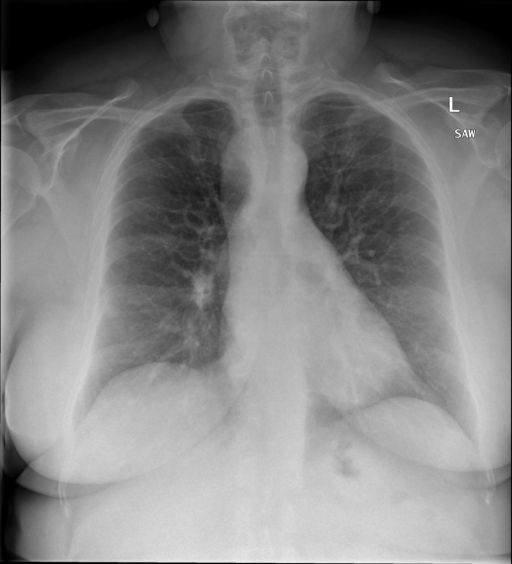

## 本文贡献  - 借助ChatGPT以及公开的数据集,我们构造了一个`X光影像-诊断报告`对的医学多模态数据集; - 我们将构建的中文胸部X光片诊断数据集在[VisualGLM-6B](https://github.com/THUDM/VisualGLM-6B)进行微调训练,并开放了部分训练权重用于学术研究; ## 数据集 - [MIMIC-CXR](https://physionet.org/content/mimic-cxr-jpg/2.0.0/)是一个公开可用的胸部X光片数据集,包括377,110张图像和227,827个相关报告。 - [OpenI](https://openi.nlm.nih.gov/faq#collection)是一个来自印第安纳大学医院的胸部X光片数据集,包括6,459张图像和3,955个报告。 在上述工作中,报告信息都为非结构化的,不利于科学研究。为了生成合理的医学报告,我们对两个数据集进行了预处理,并最终得到了可以用于训练的**英文报告**。除此之外,为了更好的支持中文社区发展,借助ChatGPT的能力,我们将英文报告进行了中文翻译,并最终形成了可用于训练的数据集。 |数据集|数量|下载链接| |:-|:-|:-| |MIMIC-CXR-zh|-|-| |OpenI-zh|6,423|[诊疗报告(英文)](./data/openi-en.json)、[诊疗报告(中文)](./data/Xray/openi-zh.json) 、[X光影像](https://pan.baidu.com/s/13GBsDMKf6xBZBSHpoWH_EA?pwd=k9sh)| ## 快速上手 1. 安装环境 ```bash # 安装依赖 pip install -r requirements.txt # 国内换源安装依赖 pip install -i https://mirrors.aliyun.com/pypi/simple/ -r requirements.txt ``` 此时默认会安装`deepspeed`库(支持`sat`库训练),此库对于模型推理并非必要,同时部分`Windows`环境安装此库时会遇到问题。 如果想绕过`deepspeed`安装,我们可以将命令改为: ```bash # 安装依赖 pip install -i https://mirrors.aliyun.com/pypi/simple/ -r requirements_wo_ds.txt # 安装SwissArmyTransformer pip install -i https://mirrors.aliyun.com/pypi/simple/ --no-deps "SwissArmyTransformer>=0.3.6" ``` 2. 模型推理 CLI推理: ```python python cli_demo.py --from_pretrained checkpoints/finetune-XrayGLM-05-25-01-04 --prompt_zh '详细描述这张胸部X光片的诊断结果' ``` 更多[参数](https://github.com/WangRongsheng/XrayGLM/blob/main/cli_demo.py#L16) ## 效果展示 影像诊断: |X光影像|诊疗报告(医生)|XrayGLM| |:-|:-|:-| ||根据X射线图像,心脏大小正常,肺部看起来很清晰。已经排除了肺炎、积液、水肿、气胸、腺病、结节或肿块的存在。该发现表明一切正常。换句话说,总体印象是胸部正常。|X光片显示,心脏大小正常。肺部没有气胸或胸腔积液的证据。骨骼结构看起来没有任何异常。总的来说,X光片表明没有发现急性心肺疾病的迹象。| ||X光图片显示没有扭曲的区域、可疑的骨质不透明度或胸腺积液。心脏大小轻微增大,但非常稳定。此外,没有气胸的证据,肺野也正常。总体来说,X光片显示没有急性心脏异常,但要注意轻微的心脏扩大。|X光片显示,心脏大小正常。肺部和纵隔轮廓清晰,没有气胸或胸腔积液的证据。骨骼结构完整,没有任何急性异常。| ||心影形态在正常范围内。没有急性骨质异常。有可能出现没有明显的吸水或肺实质状况的线索。没有大面积积液或气胸。有可能怀疑其有误吸或肺实质问题。为了确诊和治疗,可能需要进行适当的影像学随访。|心脏大小正常,肺部和纵隔轮廓清晰。没有急性异常或活动受限的证据。没有任何明显的气胸、胸腔积液或肺不张的迹象。此外,也没有发现任何局灶性骨质异常或其他急性疾病。| 多轮对话: |X光影像|诊疗报告(医生)| |:-|:-| ||右侧主动脉突出观察到。心脏大小正常。胸部未发现明显的肺气肿、胸膜积液或可疑的肺部病变。报告指出已知右侧主动脉情况正常。| ```bash >> X光影像路径:./data/Xray/861_1.png >> 用户:这是一张什么图? >> XrayGLM:这张图片显示的是一张肺部检查的X光片。 >> 用户:请描述这张胸部X光片的诊断结果 >> XrayGLM:心脏大小正常,肺部清晰。没有急性心肺疾病的证据。 >> 用户:是否存在肺气肿? >> XrayGLM:没有肺气肿。心脏大小正常,肺部清晰。没有发现急性心肺疾病的证据。 >> 用户:平时饮食该注意什么? >> XrayGLM:饮食应该健康,均衡。建议增加蛋白质的摄入量,因为蛋白质有助于维持肌肉和骨骼的健康。多食用蔬菜、水果、全谷物以及健康的脂肪来源如橄榄油、鱼类等可以帮助获得足够的维生素和矿物质。此外,避免过度饮酒或吸烟,这些习惯可能会对心脏健康产生负面影响。 ``` ## 未来展望 1. 模型的能力更多来源于数据的支持,`OpenI-zh`作为微调数据集,其数据量足以支持研究,在更广泛的任务和性能表现上,我们认为**在大规模数据集上预训练并在高质量少量数据集上微调是一种可行的方案**; 2. 普遍意义的理解上,视觉多模态模型=视觉模型+语言模型。除了需要关注视觉模型信息与语言模型输出的搭配外,还需要**额外关注到语言模型的加强,在人机的对话中,尤其是医疗语言模型的问答上,除了专业的医疗问题回答,带有人文情怀的有温度的回答更应该是我们追寻的目标**。 ## 项目致谢 1. [VisualGLM-6B](https://github.com/THUDM/VisualGLM-6B)为我们提供了基础的代码参考和实现; 2. [MiniGPT-4](https://github.com/Vision-CAIR/MiniGPT-4)为我们这个项目提供了研发思路; 3. ChatGPT生成了高质量的中文版X光检查报告以支持XrayGLM训练; 4. [gpt_academic](https://github.com/binary-husky/gpt_academic)为文档翻译提供了多线程加速; 5. [MedCLIP](https://github.com/RyanWangZf/MedCLIP) 、[BLIP2](https://huggingface.co/docs/transformers/main/model_doc/blip-2) 、[XrayGPT](https://github.com/mbzuai-oryx/XrayGPT) 等工作也有重大的参考意义;  这项工作由[澳门理工大学应用科学学院](https://www.mpu.edu.mo/esca/zh/index.php)硕士生[王荣胜](https://github.com/WangRongsheng) 、[段耀菲](https://github.com/IsBaSO4) 、[李俊蓉](https://github.com/lijunrong0815)完成,指导老师为檀韬副教授、[彭祥佑](http://www.patrickpang.net/)老师。 *特别鸣谢:[USTC-PhD Yongle Luo](https://github.com/kaixindelele) 提供了有3000美金的OpenAI账号,帮助我们完成大量的X光报告翻译工作 ## 免责声明 本项目相关资源仅供学术研究之用,严禁用于商业用途。使用涉及第三方代码的部分时,请严格遵循相应的开源协议。模型生成的内容受模型计算、随机性和量化精度损失等因素影响,本项目无法对其准确性作出保证。即使本项目模型输出符合医学事实,也不能被用作实际医学诊断的依据。对于模型输出的任何内容,本项目不承担任何法律责任,亦不对因使用相关资源和输出结果而可能产生的任何损失承担责任。 ## 项目引用 如果你使用了本项目的模型,数据或者代码,请声明引用: ```bash @misc{wang2023XrayGLM, title={XrayGLM: The first Chinese Medical Multimodal Model that Chest Radiographs Summarization}, author={Rongsheng Wang, Yaofei Duan, Junrong Li, Patrick Pang and Tao Tan}, year={2023}, publisher = {GitHub}, journal = {GitHub repository}, howpublished = {\url{https://github.com/WangRongsheng/XrayGLM}}, } ``` ## 使用许可 此存储库遵循[CC BY-NC-SA](https://creativecommons.org/licenses/by-nc-sa/4.0/) ,请参阅许可条款。